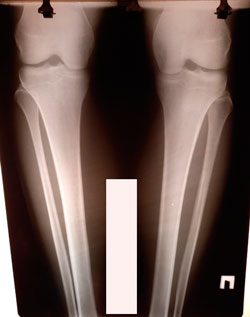

Исходник - 19 лет.

Дата операции - 19.01.2021

на фиксации